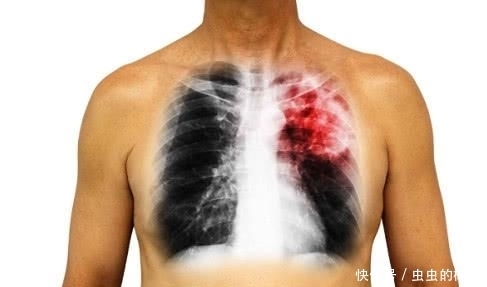

肺癌目前在国内发病率很高,每一年都有很多人患上肺癌,其实从肺病到肺癌是一个很久的变化过程,都是通过不断的积累形成的,因为很多人都不知道什么是肺癌的症状,从而错过了治疗肺癌的最佳时机。那么肺癌到底有哪些症状呢?

【 持续|身体持续出现4个症状,需警惕,或是肺癌“来袭”!】1、咳嗽

肺癌咳嗽的占有几率是30%到75%,患者往往是毫无征兆的咳嗽,且伴有胸部不适的症状,即使使用了抗生素和止咳药都起不到作用。另外,经常吸烟或老慢支的患者咳嗽的程度如果加重或频繁,需要警惕是肺癌晚期。

2、咳嗽带血

癌组织侵犯血管或癌组织小血管破裂而产生的,肺癌病人可咯血,痰中带血。

3、胸痛

出现疼痛往往提示癌症已进入中、晚期。肺癌患者胸痛是不规则的隐隐作痛,晚上会比较严重,且后来会慢慢加重,变得难以忍受,昼夜不停。

4、胸闷、气急

临床有10%的肺癌患者会有胸闷和气急的症状,这大多数患者是属于中央型肺癌患者,另外,肺功能本身就比较差的患者,若经常出现胸闷和气急的表现,千万别掉以轻心。